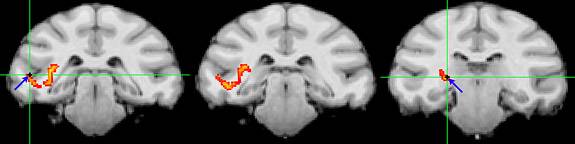

After producing neural connection maps, the researchers used electrodes (blue arrows and green crosshairs) to monitor the direct communication paths (yellow-orange) between the pulvinar and clusters of brain cells, which in this case are in the temporal lobe. Image courtesy of Science/AAAS